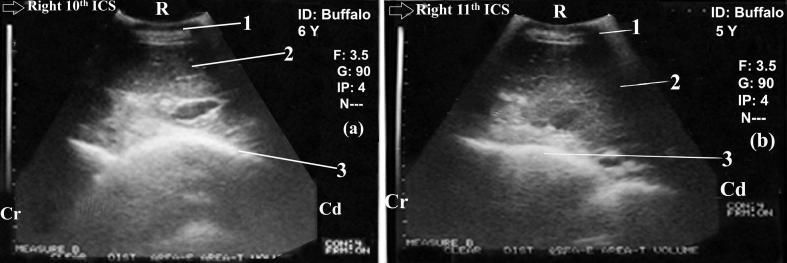

The present study was conducted to describe the clinical, laboratory and ultrasonographic findings of caecal and colonic dilatation in Egyptian buffalo (). A total number of forty buffaloes were included in the study and divided into two groups: control group ( = 20) and diseased group ( = 20). Diseased buffalo were admitted to the Veterinary Teaching Hospital at Assiut University-Egypt. Each of the diseased animals was subjected to clinical, rectal, laboratory and ultrasonographic examinations. Clinically, buffalo with dilated caecum/colon showed reduced appetite, distended right abdomen, abdominal pain and tensed abdomen. Rectal examination indicated empty rectum with the presence of mucus and dilated loop of caecum and/or colon. Buffalo with dilated caecum/colon showed significant ( < 0.05) hypoproteinemia and hypoalbuminemia with significant ( < 0.05) increase in blood serum activities of aspartate aminotransferase (AST) and alkaline phosphatase (ALK). Ultrasonographically, the dilated caecum and proximal loop of colon occupied the last right three intercostal space (ICSs) particularly their ventral part, intertangled with the liver dorsally in these ICSs. Dilated colon did not hinder the visibility of the liver. The dilated caecum/colon also filled the whole right flank region, with hiding of right kidney, loops and peristaltic movement of the small intestines. The closest wall of the dilated caecum and proximal loop of the colon was imaged as thick semi-circular echogenic line. The furthest wall and contents of dilated caecum/colon were not imaged. In conclusion, buffalo with caecal and/or colonic dilatation have non-specific clinical and laboratory findings; however the affected animals show characteristic ultrasonographic findings.

本研究旨在描述埃及水牛盲肠和结肠扩张的临床、实验室及超声检查结果。本研究共纳入40头水牛,分为两组:对照组(n = 20)和患病组(n = 20)。患病水牛被收治于埃及艾斯尤特大学兽医教学医院。每头患病动物均接受临床、直肠、实验室及超声检查。临床上,盲肠/结肠扩张的水牛表现为食欲减退、右腹膨隆、腹痛及腹部紧张。直肠检查显示直肠空虚,有黏液,盲肠和/或结肠袢扩张。盲肠/结肠扩张的水牛出现显著(P < 0.05)的低蛋白血症和低白蛋白血症,血清天冬氨酸氨基转移酶(AST)和碱性磷酸酶(ALK)活性显著(P < 0.05)升高。超声检查显示,扩张的盲肠和结肠近端占据右后三个肋间间隙(ICSs),尤其是其腹侧部分,在这些肋间间隙与肝脏背侧相互缠绕。扩张的结肠不妨碍肝脏的观察。扩张的盲肠/结肠还充满整个右腹侧区域,右肾、肠袢及小肠蠕动被遮挡。扩张的盲肠和结肠近端最靠近的壁被成像为厚的半圆形回声线。扩张的盲肠/结肠最远的壁及内容物未被成像。总之,盲肠和/或结肠扩张的水牛有非特异性的临床和实验室检查结果;然而,患病动物有特征性的超声检查结果。